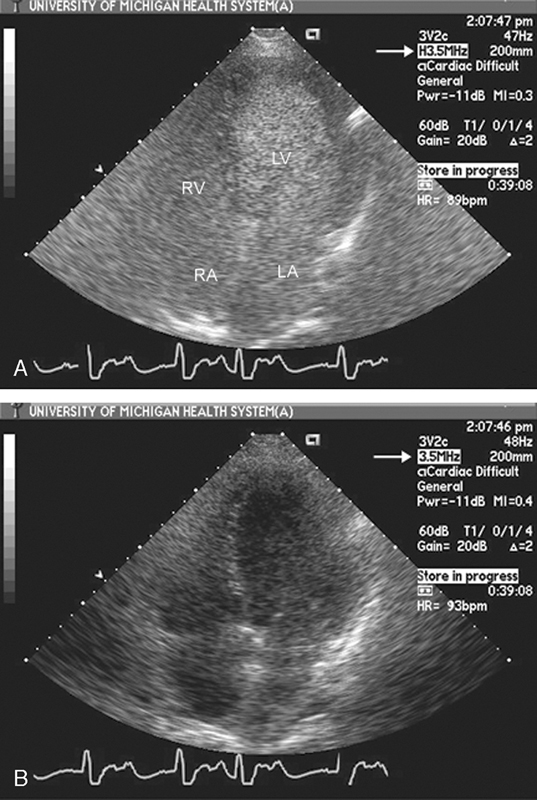

فحوصات تشخيصية لبعض امراض القلب والشرايين التاجية